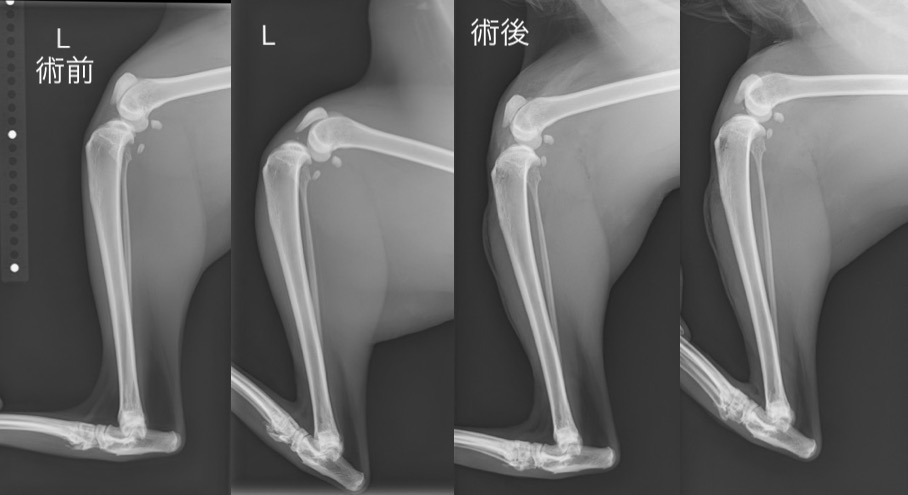

手術直後の単純X線検査画像と比較(術後は通常のラテラル像、足根関節過屈曲時ともにCrTTの消失が認められます。)